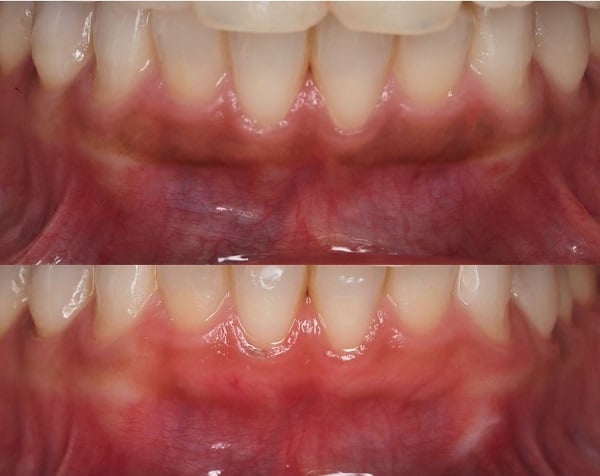

上がピーリング前、下がピーリング後です。

自然で健康的なピンク色になりました。